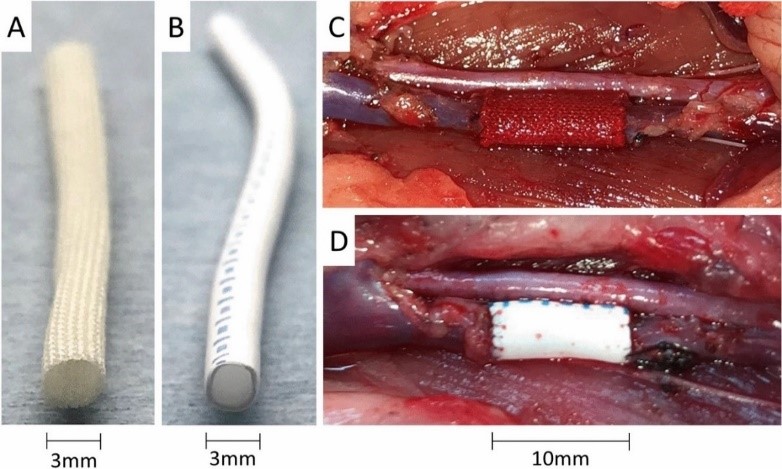

Phẫu thuật ghép mạch được sử dụng rộng rãi để điều trị những trường hợp tổn thương gây hẹp mạch nghiêm trọng (> 65% đường kính lòng mạch) hoặc thay thế đoạn mạch do phình mạch hoặc ghép tạng. Các mạch ghép được được lựa chọn thường là tự thân, đồng loài, dị loài hoặc nhân tạo. Tuy nhiên, việc sử dụng các mạch máu tự thân không phải lúc nào cũng thuận lợi và mạch được lựa chọn chủ yếu là tĩnh mạch – cơ quan thường bị xơ hóa theo thời gian (< 10 năm). Ghép mạch máu đồng loài hay từ mạch in bằng công nghệ 3D là hướng lựa chọn tốt với những hy vọng như mạch có thể phát triển theo kích thước mô tạng, tuy nhiên cũng gặp khó khăn do tương thích miễn dịch. Mạch máu nhân tạo ví dụ như mạch Dacron và Teflon (expanded polytetrafluoroethylene – ePTFE) được sử dụng phổ biến trong điều trị, tuy nhiên kích thước nhỏ nên hiệu quả thấp. Bên cạnh đó, mạch nhân tạo có thể gặp biến chứng như chảy máu, hẹp lòng đoạn mạch cấy ghép, nhiễm trùng vết thương, phình mối nối, dị ứng, phản ứng miễn dịch, đặc biệt là sẽ hẹp tương đối khi cơ thể còn phát triển, v.v. Vì vậy, đến nay chưa có mạch nhân tạo hoàn hảo.

Hiện nay, nguồn cung cấp các mạch ghép có đường kính nhỏ (< 5mm) (small-diameter vascular grafts – SDVG) đặt ra thách thức đáng kể trong điều trị các bệnh lý mạch máu. Các mạch máu nhân tạo có tỷ lệ thành công cao trong ghép các mạch máu kích thước lớn, nhưng chưa có hiệu quả đối với các mạch nhỏ. Những vấn đề thường gặp khi ghép mạch máu nhỏ bao gồm lòng mạch bị thu hẹp hoặc tắc mạch máu, phình mạch. Tốc độ dòng máu thấp ở những mạch có đường kính nhỏ sẽ dẫn đến tăng các phản ứng bất thường giữa máu và đoạn mạch mới ghép.

Tuy nhiên, việc sử dụng trực tiếp các mạch khử tế bào để ghép vẫn còn nhiều thách thức liên quan đến hiện tượng phình động mạch, rối loạn huyết động và tắc nghẽn mạch máu, dẫn đến tỷ lệ sống sót của vật chủ thấp. Trong nghiên cứu của Gui và các cộng sự, các mạch dây rốn khử tế bào trước ghép có đường kính trong là 1,5 mm (tại áp lực zero), khá tương đồng với kích thước động mạch chuột cống (khoảng 1 mm). Tuy nhiên, đường kính mạch tăng lên nhanh chóng và đạt xấp xỉ 4,5 mm sau khi ghép (Hình 5).

Sau một quá trình nghiên cứu và thử nghiệm, chúng tôi đã xây dựng được một quy trình xử lý mạch tiền ghép và quy trình ghép mạch dị loài từ động mạch dây rốn vào động mạch chủ bụng dưới thận chuột cống trắng thành công. Các động mạch dây rốn sau khi thu nhận và xử lý tiền ghép không gây kích thích tăng sinh tế bào T khi tiếp xúc với các tế bào bạch cầu đơn nhân của máu chuột cống, không kích thích biểu hiện các yếu tố chỉ thị trạng thái hoạt hóa của tế bào T (còn gọi là tế bào lympho T – là một loại bạch cầu thuộc dòng tế bào lympho, đóng vai trò quan trọng trong hệ thống miễn dịch đáp ứng của cơ thể) như IL1-β, IFN-α, và TNFα. Hơn nữa, phân tích giải phẫu bệnh cho thấy chỉ có sự đáp ứng viêm nhẹ khi mạch dây rốn được cấy vào lớp mỡ dưới da chuột cống sau 30 ngày. Những kết quả này cho thấy, động mạch dây rốn tươi có tính sinh miễn dịch thấp, phù hợp cho việc ghép trên chuột cống.

Kết quả ghép dị loài cho thấy, 100% chuột ghép mạch dây rốn người (10/10) đều có khả năng sống trên 4 tuần sau ghép. Đáng chú ý, không nhận thấy hiện tượng tắc mạch hay huyết khối xảy ra trong mạch ghép dựa trên các kết quả siêu âm định kỳ sau 3, 7, 21, và 30 ngày sau ghép. Thêm vào đó, mặc dù có sự không hoàn toàn phù hợp về kích thước, do đường kính mạch dây rốn lớn hơn động mạch chủ của chuột cống, tương tự như các báo cáo đã công bố, nhưng trong nghiên cứu này, kết quả siêu âm cho thấy đường kính trong lòng mạch khá ổn định theo thời gian, không thấy sự tăng rõ rệt về kích thước như trong nghiên cứu của Gui và cộng sự. Đồng thời, lưu lượng máu lưu thông trong mạch ghép khá tương đồng với động mạch chủ chuột tại hai đầu nối mạch. Đánh giá vi thể, các chỉ số sinh lý, hóa sinh, và phản ứng miễn dịch cho thấy mảnh ghép hòa hợp với cơ thể nhận và thực hiện chức năng như các mạch máu bình thường của cơ thể. Các kết quả đánh giá hoạt động chức năng vận động của chuột ghép cho thấy sự tương đồng với đối chứng trong suốt quá trình thí nghiệm. Quy trình ghép và chuột ghép dị loài đã được nhóm nghiên cứu đăng ký sáng chế với Cục Sở hữu trí tuệ (đã được chấp nhận đơn và đang trong quá trình xem xét cấp bằng).